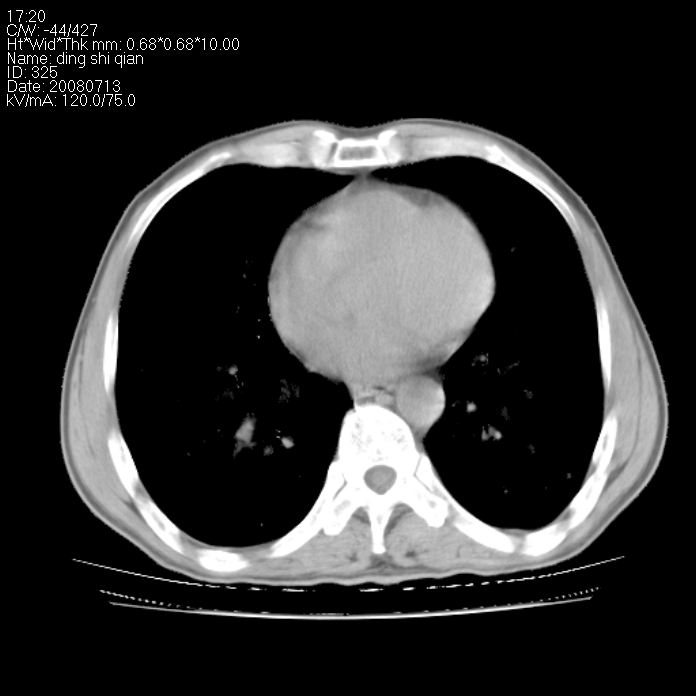

标题: CT14654:男 50岁 近来胸痛 [打印本页]

标题: CT14654:男 50岁 近来胸痛

右侧上肺块状软组织影,浅分叶,边缘毛刺证,与胸膜粘连,考虑:周围性肺癌

右肺上叶周围型肺癌可能性大。

右侧上肺块状软组织影,浅分叶,边缘毛刺证,与胸膜粘连,考虑:周围性肺癌!支持!

典型右肺周围型肺癌

首先考虑周围性肺癌,建议强化或穿刺明确

考虑: 右肺上叶周围型肺癌可能性大.

右肺上叶周围型肺癌。